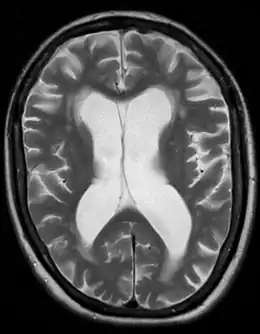

Atrophie cérébrale due à une démence vasculaire

La démence vasculaire est un trouble qui peut être causé par une occlusion des artères cérébrales, par la perte de tissu cérébral consécutive à de multiples petits accidents vasculaires cérébraux (AVC) parsemés dans le cerveau ou à un accident ischémique constitué, par une angiopathie amyloïde ou encore par la maladie de Binswanger qui consiste en apparition des lésions de la substance blanche sous-corticale induites par une hypertension artérielle. Cet état engendre toutes sortes de symptômes cognitifs y compris des troubles de mémoire[1],[2].